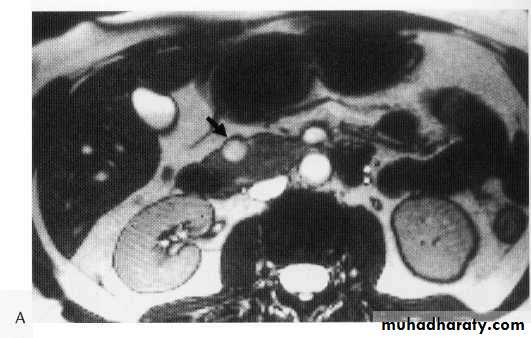

Chrons disease

Chrons stricture

Stricture + pericolic abscess